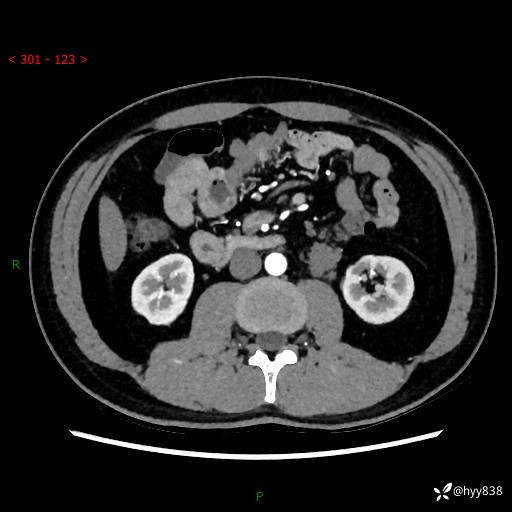

现病史:患者3月余前检查发现左侧腹膜后占位,大小约3.7*4.9cm,平素无腰疼,无肉眼血尿,无尿频尿急等不适,当时未特殊处理,在门诊复查CT提示左侧腹膜后占位,门诊拟“左侧腹膜后占位”收入院。 起病以来,患者精神佳,饮食、睡眠良好,大小便正常,体力体重无明显变化。

腹膜后CT平扫+增强